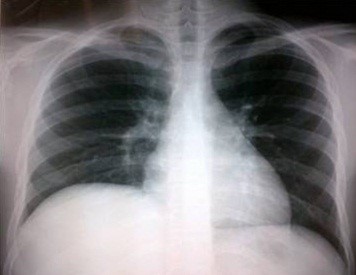

Volver a los detalles del artículo Absceso hepático amebiano con empiema pleural derecho. A propósito de un caso